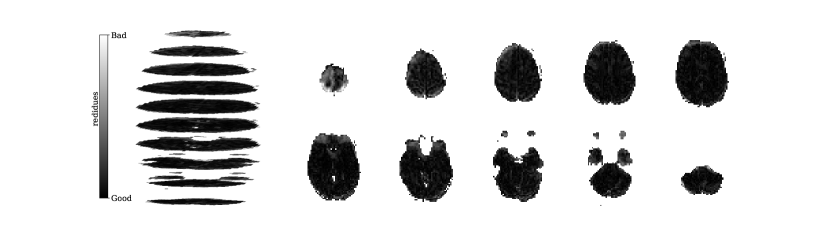

Figure 2 illustrates the distribution of residues (observed vs. estimated differences) on the fMRI volumes for the NODDI dataset. Clearly, by visual inspection, (iv) model has the darker and biggest area of shaded regions, which implies a better coverage across the brain regions and better synthesis quality. Models with topographical attention, (ii) and (iv), corresponding to Figures 2(b) and 2(d), respectively, significantly improve the synthesis, as shown by the darker and bigger areas against (i) and (iii) depicted in Figures 2(a) and 2(c), respectively. Particularly, we notice that models (i) and (iii) report difficulty in the retrieval of haemodynamical activity located in occipital and parietal lobes.

To better address which regions our baselines had more difficulty retrieving, the normalized residues were computed and are illustrated in Figure 3. Baselines – corresponding to models (i) and (ii), shown in Figures 3(a) and 3(b) respectively, which correspondingly implement a linear projection in the latent space and topographical attention –, have difficulty retrieving the prefrontal, occipital and parietal lobes, as the shade tends to a lighter grey in that region. Model (iv), shown in Figure 3(d), does not show a noticeable region with a lighter tone of grey, which implies no evident difficulty in retrieving haemodynamical activity across the different brain regions.